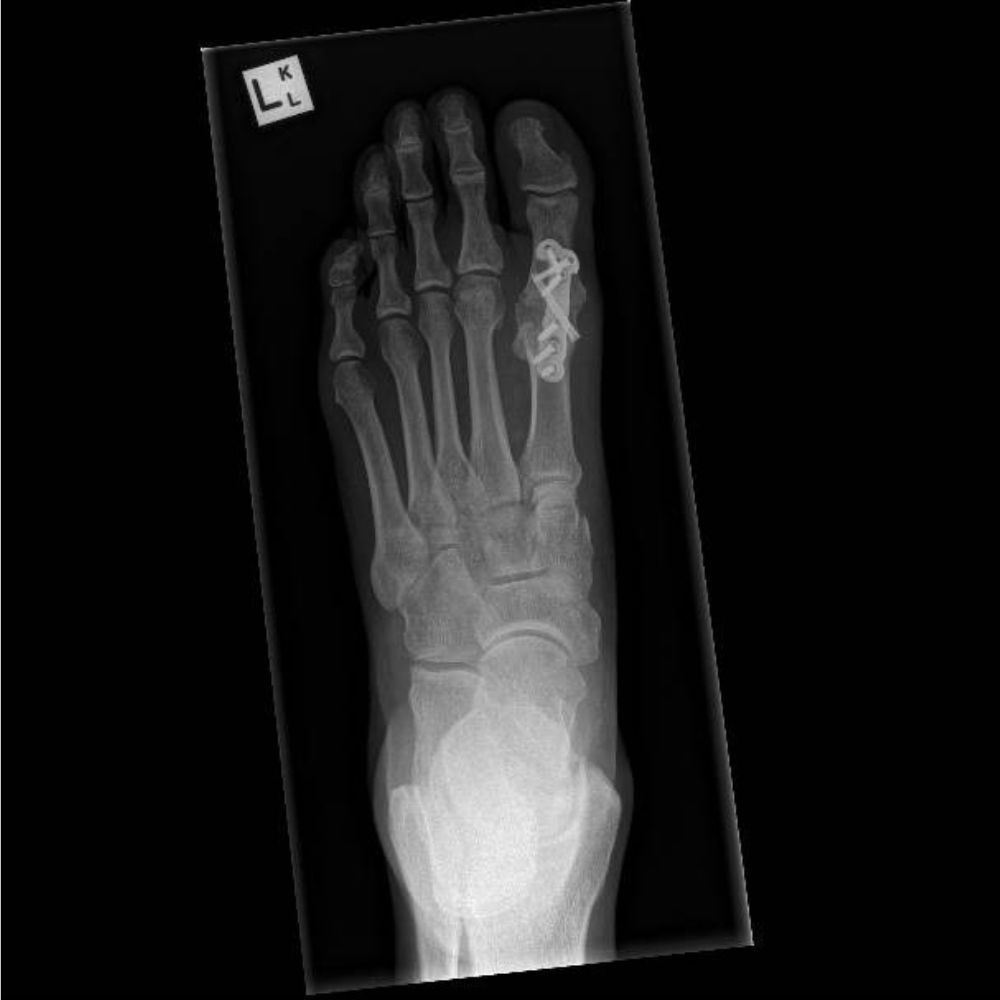

Adult Patient with Minimally Invasive Bunion Correction and Hammer Toe Correction for Metatarsalgia

Adult with Fusion (Arthrodesis) of the Left Hallux Rigidus (Osteoarthritis of the Big Toe)